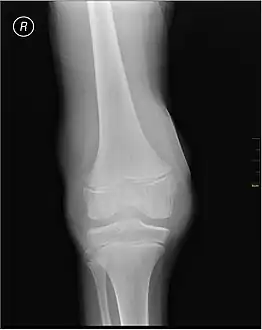

X-Ray- haemoarthritis -

Haemarthrosis on lateral view

Muscle and joint haemorrhages – or haemarthrosis – are indicative of haemophilia,[11] while digestive tract and cerebral haemorrhages are also germane to other coagulation disorders.

Repeated bleeds into a joint capsule can cause permanent joint damage and disfigurement resulting in chronic arthritis and disability. Joint damage is not a result of blood in the capsule but rather the healing process. When blood in the joint is broken down by enzymes in the body, the bone in that area is also degraded, this exerts a lot of pain upon the person afflicted with the disease.[12][13][14]